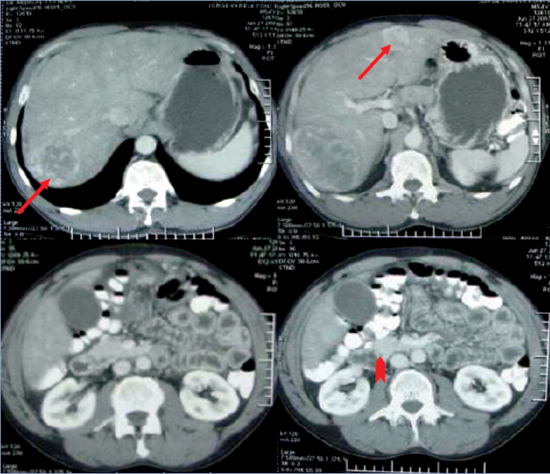

Para la localización del tumor primario y otras posibles localizaciones secundarias se solicitó cintigrama con In111 octeotride-DOTATOC, el que reveló nódulos hepáticos y captación en flanco derecho con receptores activos de somatostatina, y PET-CT Ga-68 DOTATATE que mostró hipercaptación multifocal en hígado e intestino delgado; ambos imágenes eran compatibles con carcinoide de íleon terminal con metástasis hepáticas (Figura 2). La radiografía de tránsito intestinal también ubicó la lesión a nivel del íleon distal.

Figura 2. PET-TC Ga-68 DO-TATATE muestra hipercaptación multifocal en hígado e intestino delgado (flecha) compatible con carcinoide metastásico.